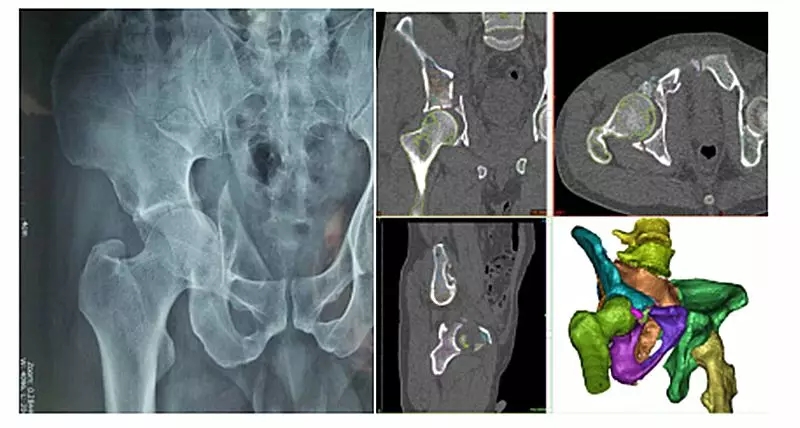

近日,我院骨外科收治一名复发骨盆骨折患者,男性,47岁,主因摔伤3小时右髋部疼痛、肿胀伴活动障碍入院。诊断为:右侧髂骨骨折、右侧髋臼粉碎性骨折、右侧耻骨骨折。经过仔细阅片后,骨外科主任焦建宝、副主任医师薛金伟认为该患者右侧骨盆存在多处骨折,且骨折断裂、移位严重。有必要应用三维可视化辅助进行术前规划及术中指导。我院医学3D影像打印中心副主任张珂经重建后发现本例患者右侧髂骨、髋臼、耻骨碎成13处之多,且多处碎骨存在移位,移位角度偏大。三维重建及手术过程都极为复杂。张珂针对该例患者连夜进行科研攻关,在最短时间重建出准确的骨盆可视化模型,并上传至三维数字云平台方便手术医生随时查看。经过精心术前规划与演练,薛金伟为患者行右侧髂骨、髋臼、耻骨骨折切开复位内固定术。患者手术顺利,手术时间较传统阅片定位后再手术的方法大大缩短,术中C型臂透视可见骨折对位、对线良好,内固定位置良好、稳定。手术结果符合术前三维重建规划预期。目前患者骨折复位质量及骨盆功能均得到良好恢复。